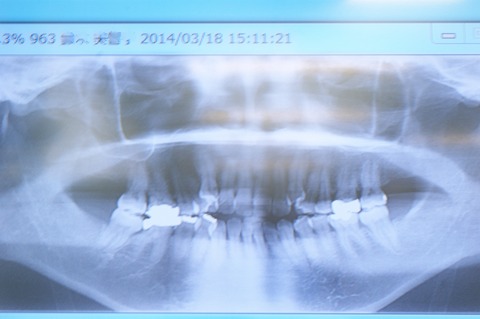

約8年前の矯正治療以前の写真と比較してみました。

矯正前は顎の大きさに比して歯が多すぎるため、林立して歯を支える歯槽骨が不均等であるのに比べ、矯正後は歯が適当な間隔を保って位置し、結果歯槽骨が均等に歯を支えている様子が確認できます。

これこそ、矯正治療が歯の健康に貢献する大きな要点の一つなのです。